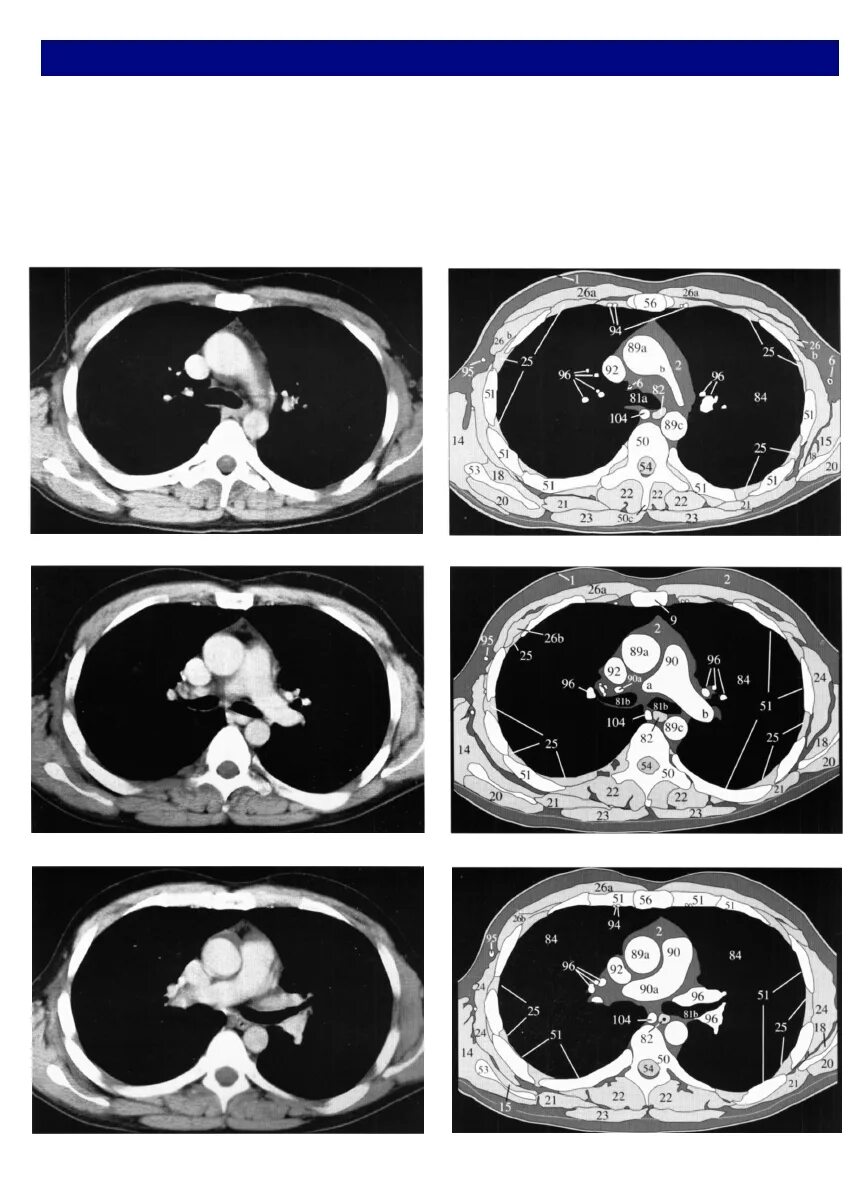

Легочный ствол на кт